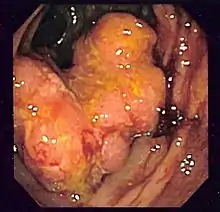

Для діагностування КРР застосовуються ендоскопічні методи дослідження: колоноскопія та ректороманоскопія під час яких лікар-ендоскопіст визначає підозріле утворення товстої кишки. Під час ендоскопічного дослідження виконується біопсія підозрілого на КРР утворення з подальшим патогістологічним аналізом біоптату.[11] Менш чутливим методом є пасаж барію з подальшим рентгенологічним дослідженням товстої кишки. Комп'ютерна томографія, МРТ та ПЕТ застосовуються при підозрі наявності віддалених метастазів КРР.